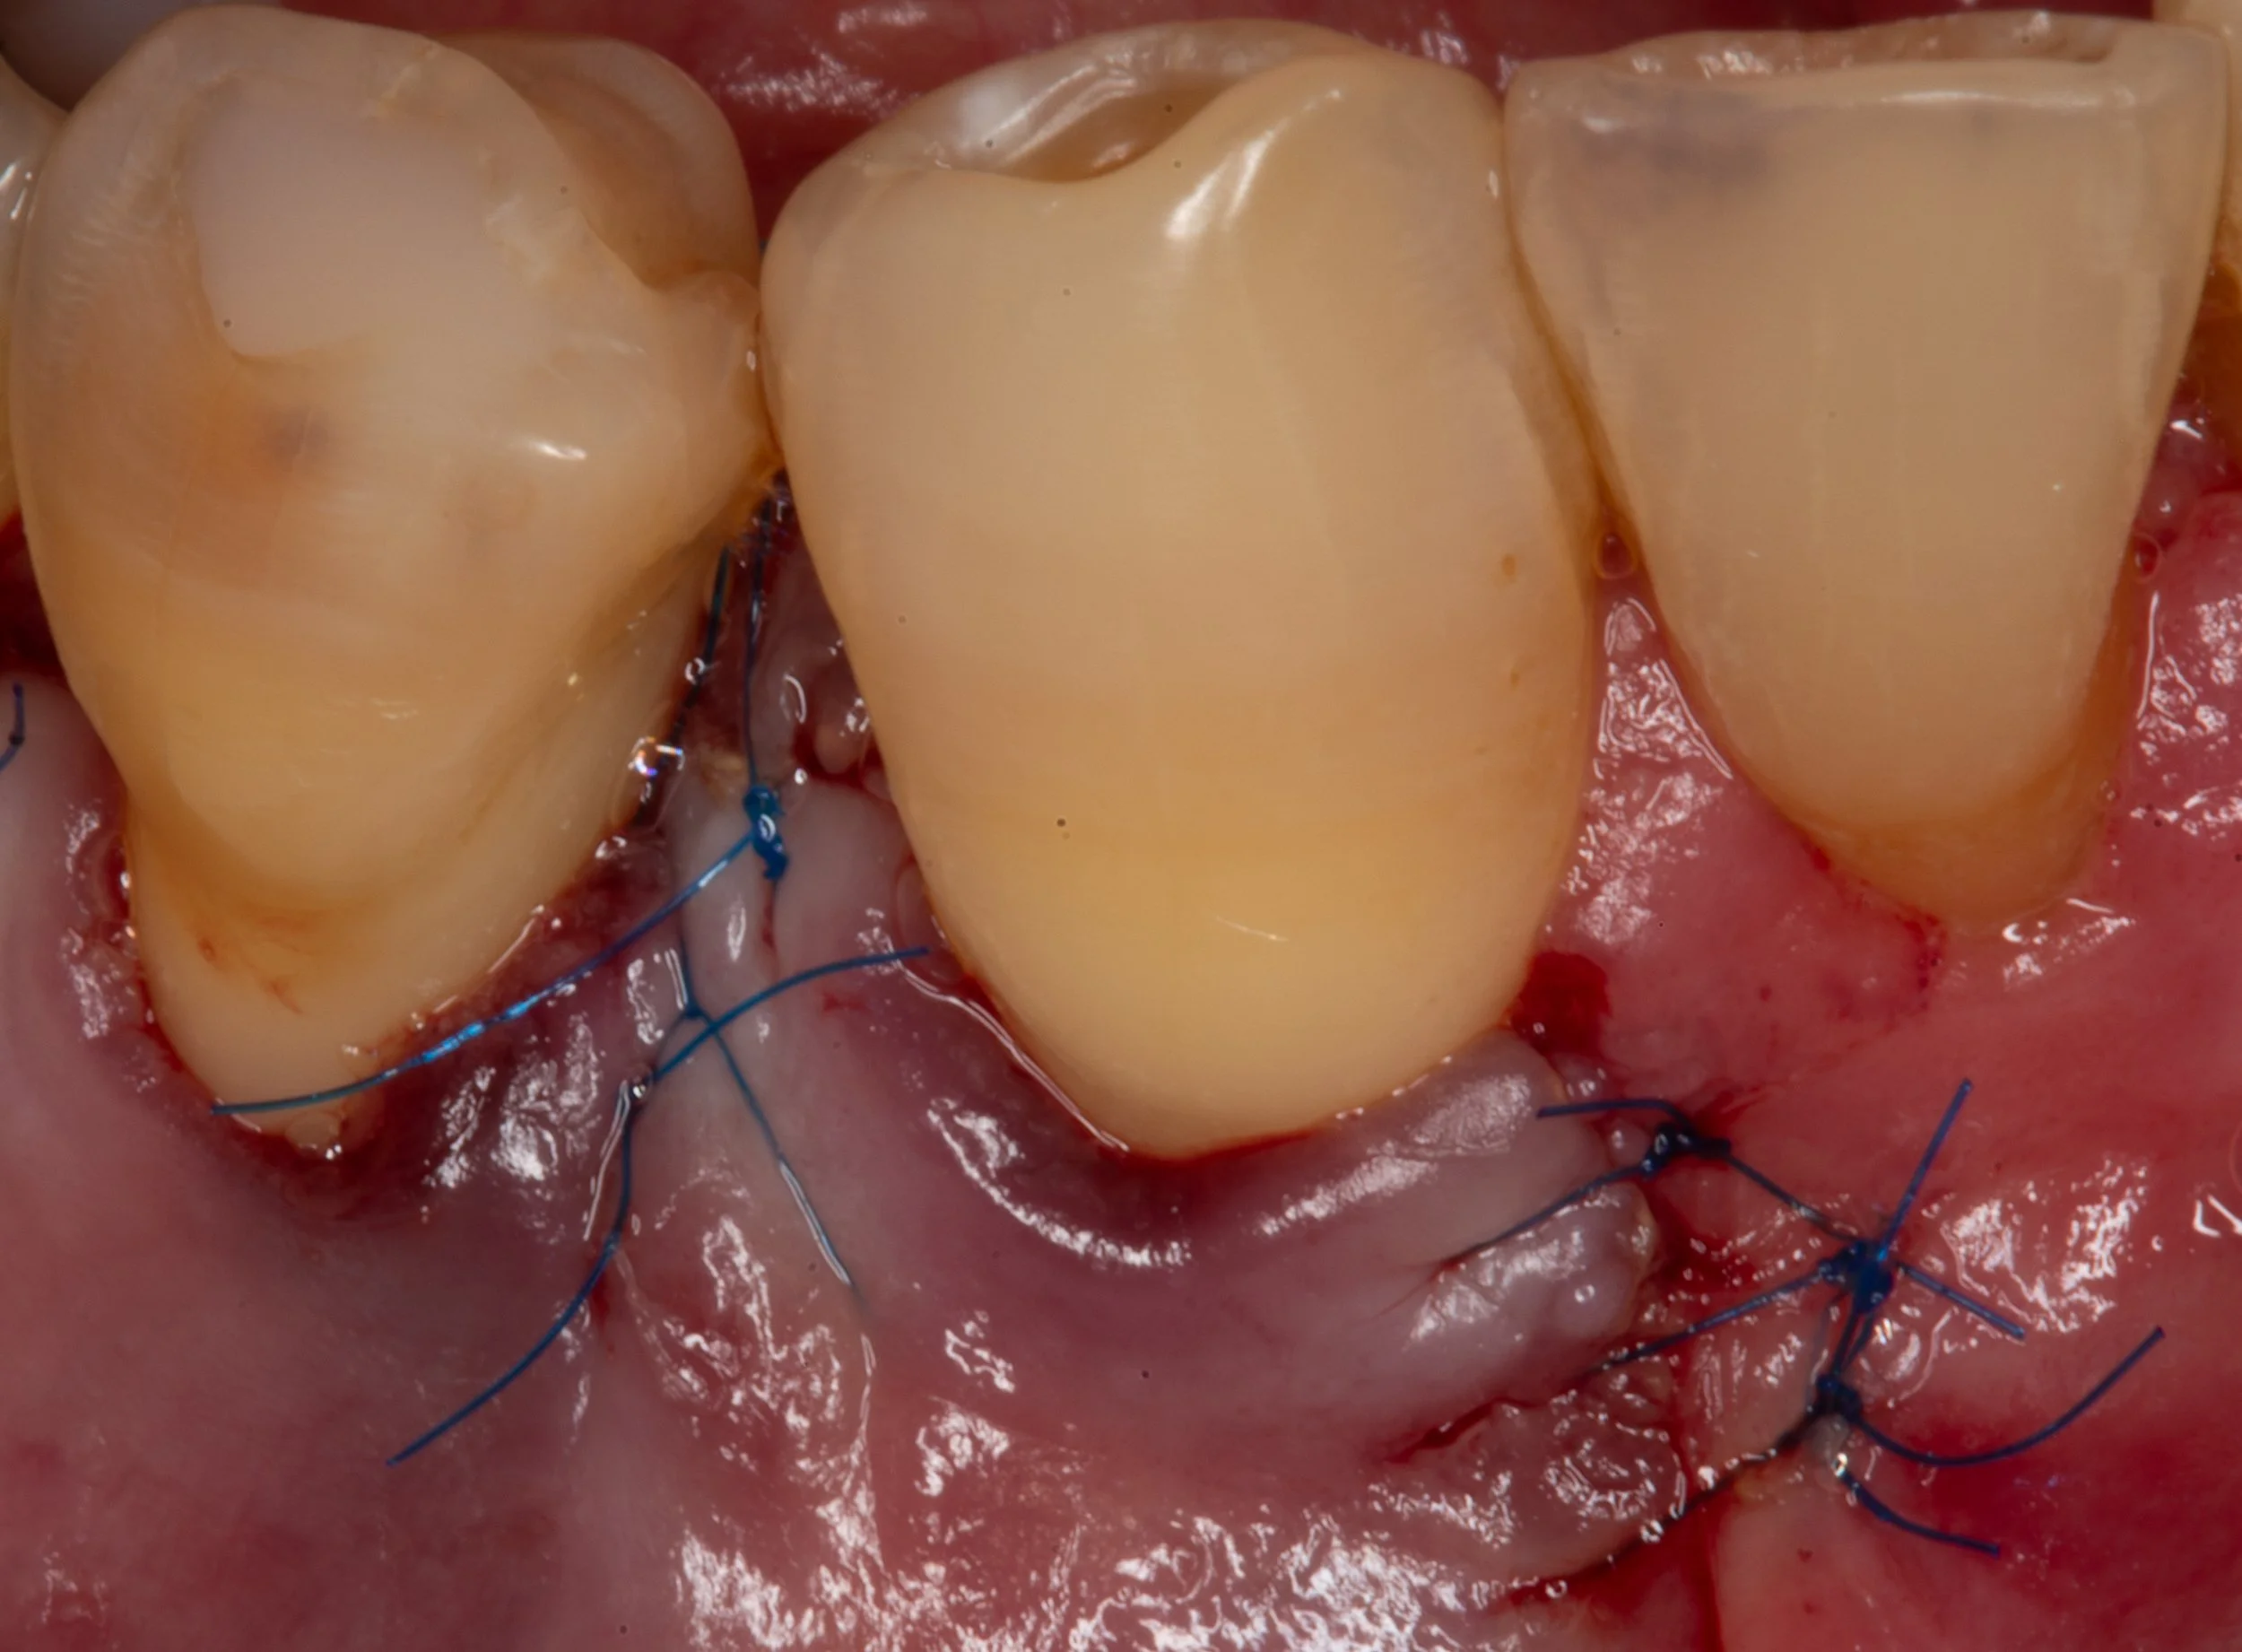

Periodontal disease will cause more bone loss until the bacteria have been removed. In this scenario, a bone graft was obtained from a tissue bank and used to rebuild the lost bone and tooth support.

The treatment of periodontal disease is generally performed under local anesthesia in an outpatient setting. Initial healing can be expected in 2-weeks with minimal discomfort and interruption to your daily activities. Complete healing and return to regular, frequent cleanings is expected after 3-4 months.

Periodontal gum disease healing after surgery